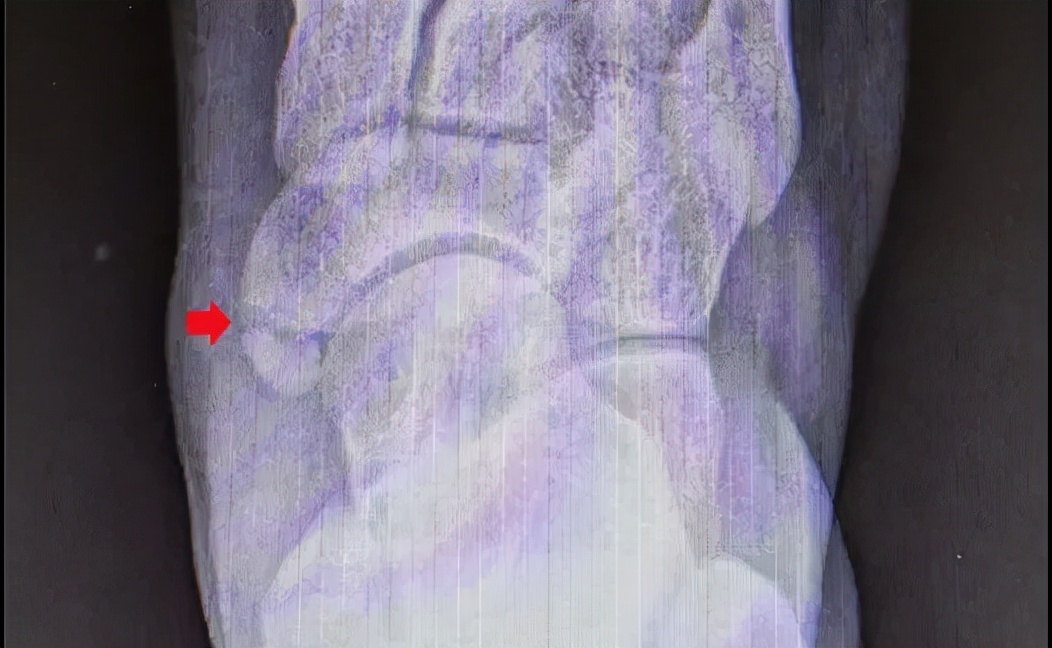

副舟骨医学影像下(X线)下的表现

I型:副舟骨成圆形,独立,与足舟骨骨接触,通常不引起症状。

II型:副舟骨呈圆形或者三角形,通过纤维软骨与足舟骨相连,常引起足内侧疼痛。

III型:副舟骨与足舟骨骨性连接,由于在骨性突起上形成疼痛,因此偶尔会出现症状。